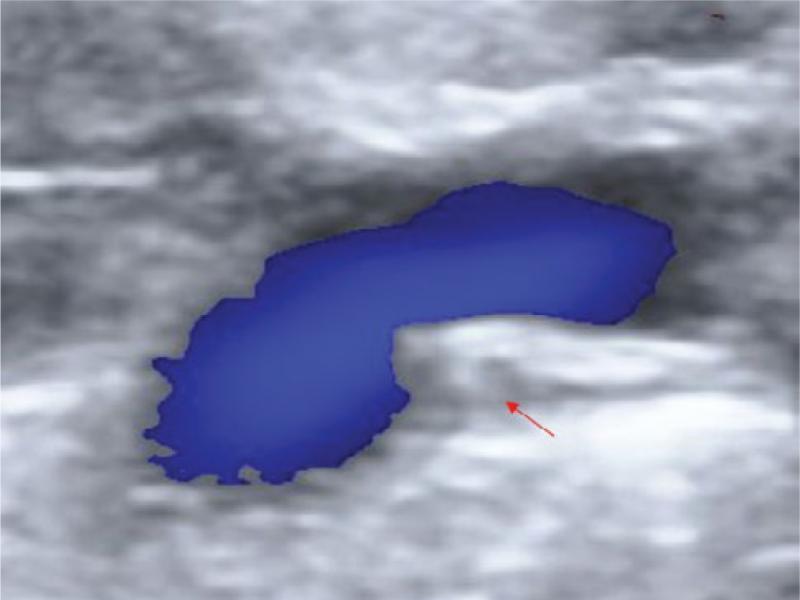

Fig. 3.

Ultrasonography of the thoracic duct. Thoracic duct (red arrow)